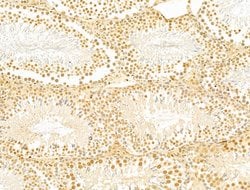

Invitrogen™ GABPB1 Polyclonal Antibody

Antibody detects endogenous levels of total GABPB1.

| Immunohistochemistry (Paraffin), Western Blot, Immunocytochemistry | |

| A synthesized peptide derived from human GABPB1(Accession Q06547), corresponding to amino acid residues V264-D314. | |

| Human, Mouse, Rat | |